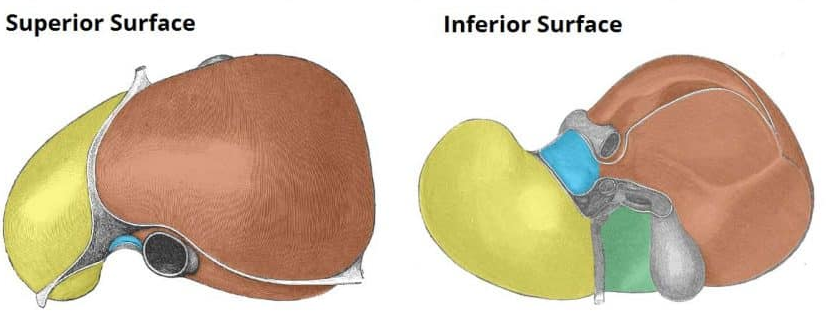

Right liver lobe

orange highlight

Left liver lobe

yellow highlight

Falciform ligament

Coronary ligament

Round ligament

Caudate lobe

blue highlight

Quadrate lobe

green highlight

Porta hepatis

What do all these make up (this is the posterior liver)

Inferior vena cava

Hepatic artery

Hepatic portal vein

Fundus of gallbladder

orange highlight

Body of gallbladder

green highlight

Neck of gallbladder

yellow highlight

Cystic duct

pink highlight

Left hepatic ducts

Right hepatic ducts

Common hepatic duct

Common bile duct

Duodenal papilla within duodenum